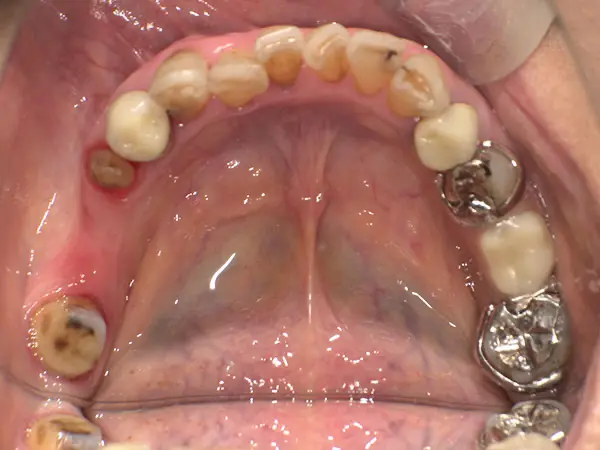

叢生、舌側矯正

術前上顎

術前下顎

術後上顎

術後下顎

| 主訴 | 上下の歯のでこぼこ |

| 診断名あるいは主な症状 | 叢生 |

| 初診年齢 | 24歳 |

| 治療内容・装置 | マルチブラケット装置(上は裏側、下は表側からの矯正治療) 歯科矯正用アンカースクリュー |

| 抜歯・非抜歯 | 上顎左右第一小臼歯抜歯 |

| 治療期間 | 1年2か月 |

| 費用 | 1,240,000円(税込) |

| 治療のリスク・副作用 | 歯の移動に伴う痛み 上下顎前歯部の歯根吸収 装置による口内炎 ブラッシング不良によるむし歯、歯周炎 |